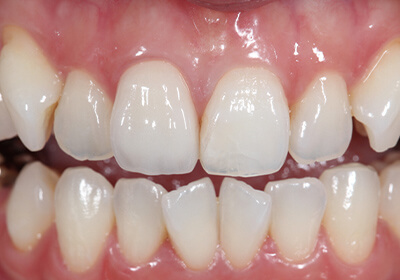

Case 01天然歯

ジルコニアレイアリング